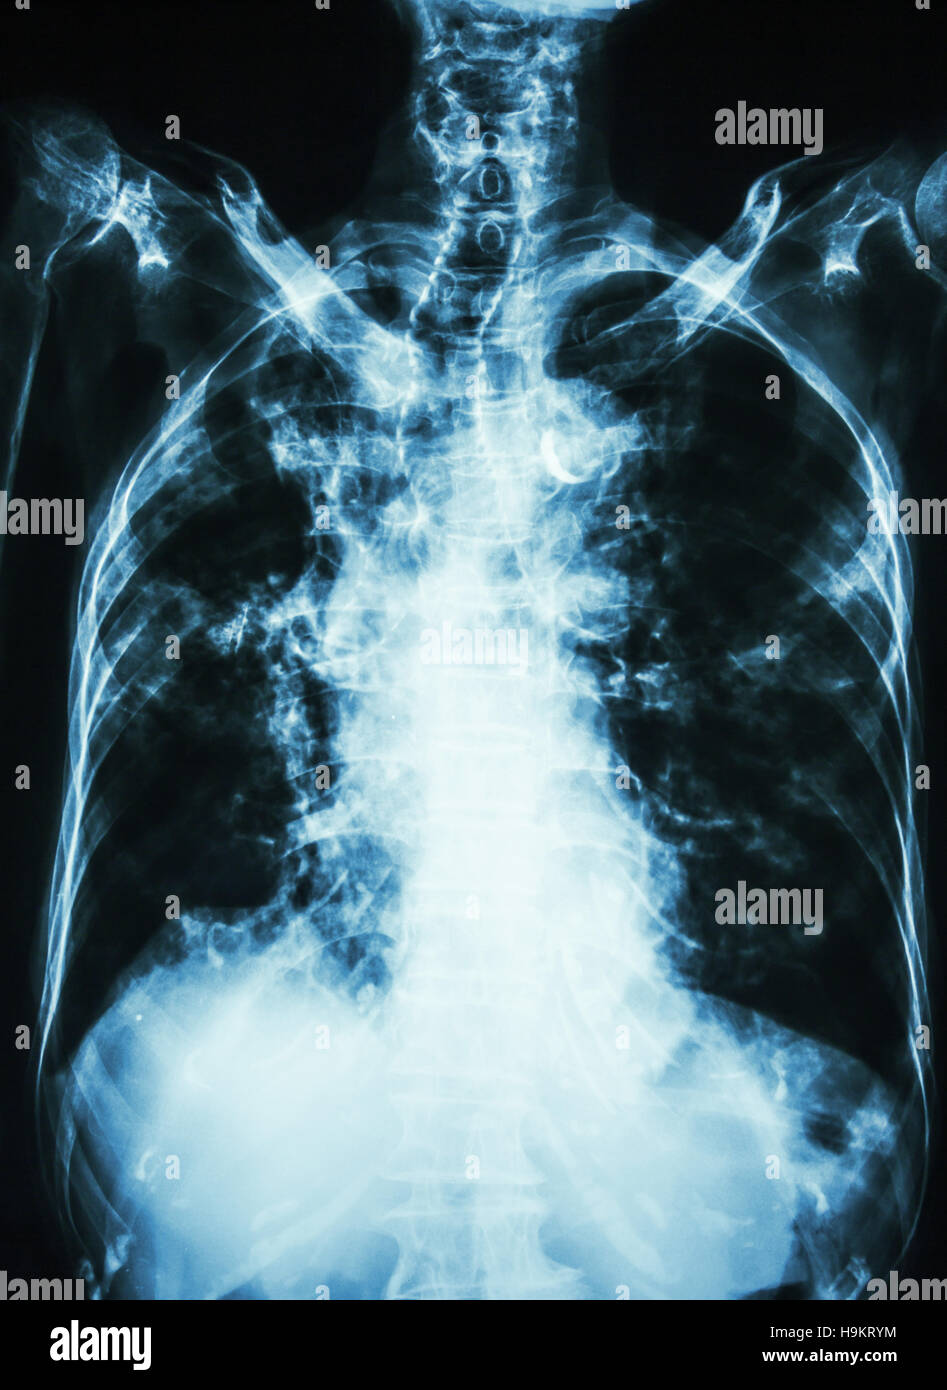

Chest X Ray Of Tb Patient . Abnormalities on chest radiographs may be suggestive of, but are never diagnostic of tb, but can be used to rule out pulmonary tb. because of these limitations, imaging plays an important role in evaluation of chest tb (ctb) patients and ct is more sensitive than cxr in this regard. [ 3, 4] for optimal management, the radiologists are often.

because of these limitations, imaging plays an important role in evaluation of chest tb (ctb) patients and ct is more sensitive than cxr in this regard. Abnormalities on chest radiographs may be suggestive of, but are never diagnostic of tb, but can be used to rule out pulmonary tb. [ 3, 4] for optimal management, the radiologists are often.

Chest X Ray Of Tb Patient Abnormalities on chest radiographs may be suggestive of, but are never diagnostic of tb, but can be used to rule out pulmonary tb. [ 3, 4] for optimal management, the radiologists are often. because of these limitations, imaging plays an important role in evaluation of chest tb (ctb) patients and ct is more sensitive than cxr in this regard. Abnormalities on chest radiographs may be suggestive of, but are never diagnostic of tb, but can be used to rule out pulmonary tb.